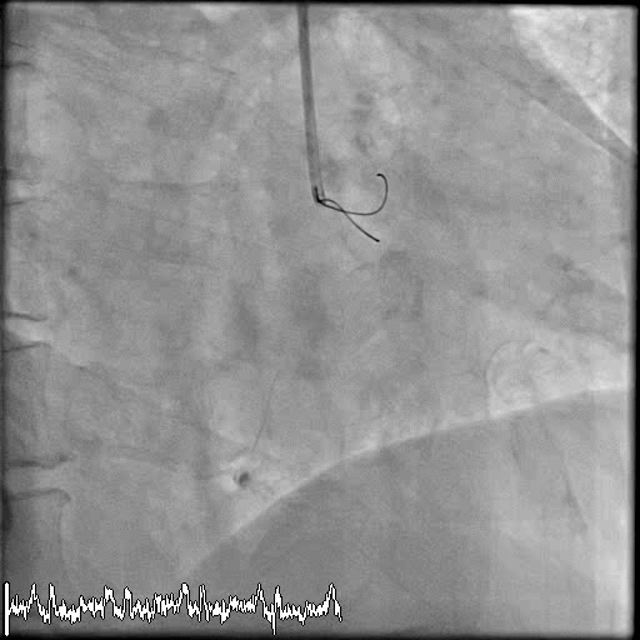

During extreme stress, there is an increase in core body temperature, imbalance of the salts within our body, direct damage to the heart and more. This may lead to dangerous heart rhythms (Ventricular Fibrillation) such as the one above (Figure 3). Fortunately for the patient, trained medical personal was present during the collapse with a defibrillator at hand and thus the patient was rapidly resuscitated, made a full recovery and continues to engage in an active lifestyle. The patient subsequently had very comprehensive heart scans and tests which showed that the heart was completely normal. Hence even with a normal heart tests, we tell all athletes to know their limits and to ensure adequate training for the competition or adventure that they are planning to take part in.